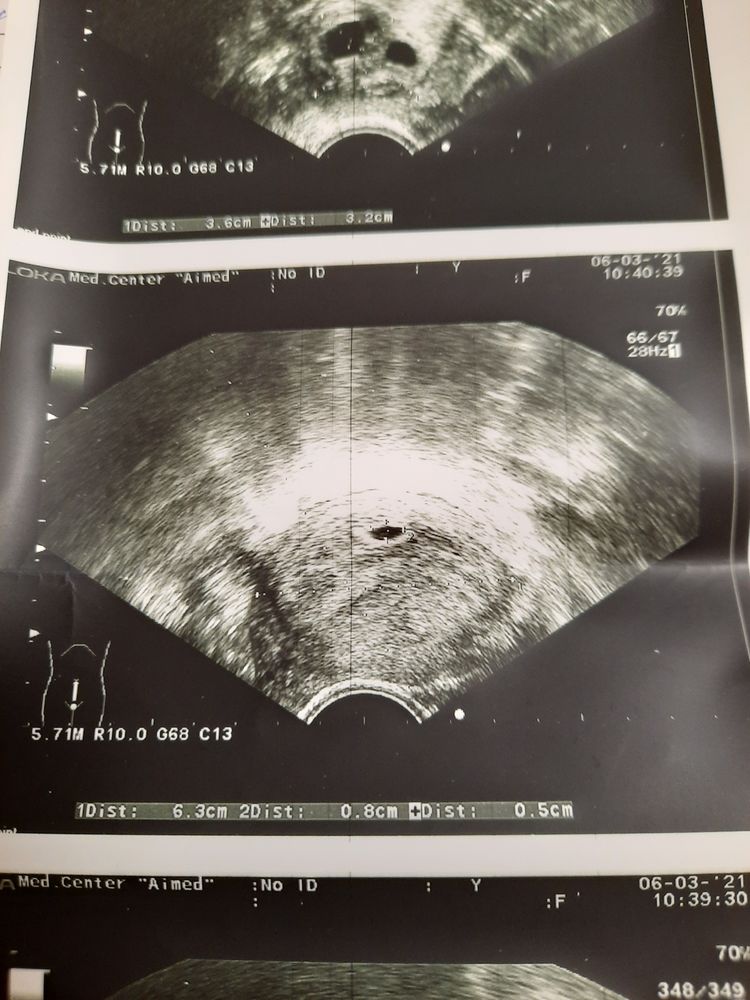

Julia Tim, просто РЕ на узи озвучила 13.5 мм, а написала 7мм. Вот я и думаю, какой все таки размер.

Татьяна Родина, вы у врача уточните лучше)) но мне кажется что ваше пя 0.8 на 0.5)